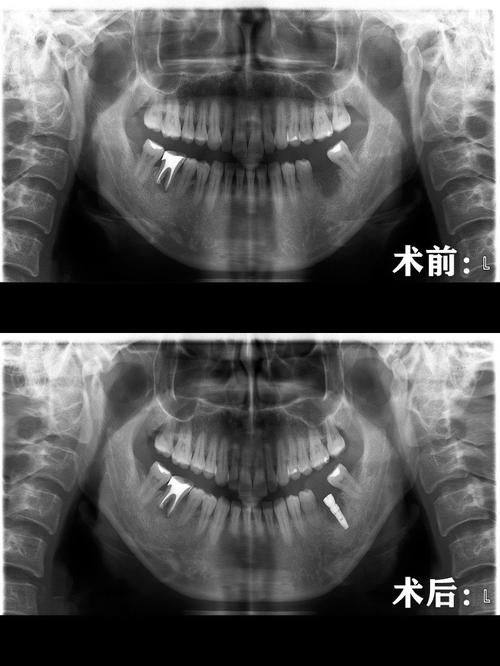

牙齿种植:针对牙齿缺失问题,采用合适的种植体,医生经验多,种植后牙齿功能接近天然牙,稳定性强。